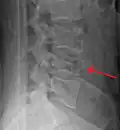

A burst fracture is a type of traumatic spinal injury in which a vertebra breaks from a high-energy axial load (e.g., traffic collisions or falls from a great height or high speed, and some kinds of seizures), with shards of vertebra penetrating surrounding tissues and sometimes the spinal canal.[1] The burst fracture is categorized by the "severity of the deformity, the severity of (spinal) canal compromise, the degree of loss of vertebral body height, and the degree of neurologic deficit."[2] Burst fractures are considered more severe than compression fractures because long-term neurological damage can follow. The neurologic deficits can reach their full extent immediately, or can progress for a prolonged time.

Diagnosis is by medical imaging.